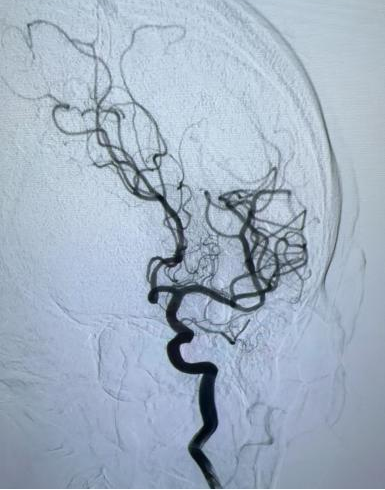

在DSA(数字减影血管造影)引导下,团队凭借丰富经验和娴熟技术,精准将取栓支架送达栓塞部位。随着支架撤出,一团致命血栓被成功取出!手术从股动脉穿刺到血流完全恢复,全程仅用30分钟。